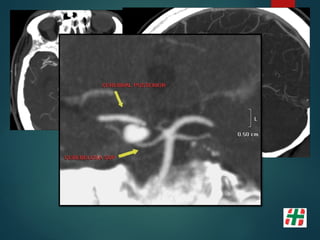

Patología Aneurismática

 Dilatación vascular que afecta solo una porción del

perímetro vascular.

 Carece de lámina elástica y ± túnica media.

 Se los clasifica básicamente en:

 Sacular;

 Ampollar;

 Fusiforme.

Patología Aneurismática  Dilataciónvascular que afecta solo una porción del perímetro vascular.  Carece de lámina elástica y ± túnica media.  Se los clasifica básicamente en:  Sacular;  Ampollar;  Fusiforme.

• 23.

Pericallosa 4% Comunicante Anterior30% Bifurcación ACI 7.5% ACM 20% Comunicante Posterior 25% Tope Basilar 7% PICA 3% Otras 3,5% Brisman, et al. N Engl J Med 2006;355:928-39.

Métodos diagnósticos  AngiografíaDigital (3D DSA); Sensibilidad del 96% lesiones del 0.5 a 4 mm.  TC, Angio TC (Multidetector); Sensibilidad del 40% al 97%.  Angio RM (T.O.F.) Sensibilidad 38% lesiones al 94%